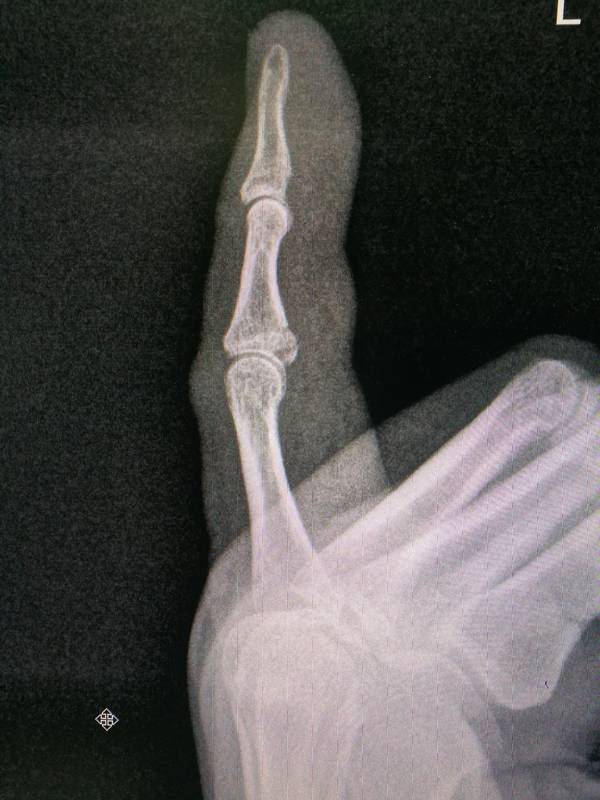

我的第一次骨折是小指中节指骨基底掌侧骨折

IMG_20180702_075109.jpg

IMG_20180702_075122.jpg

IMG_20180701_175255.jpg